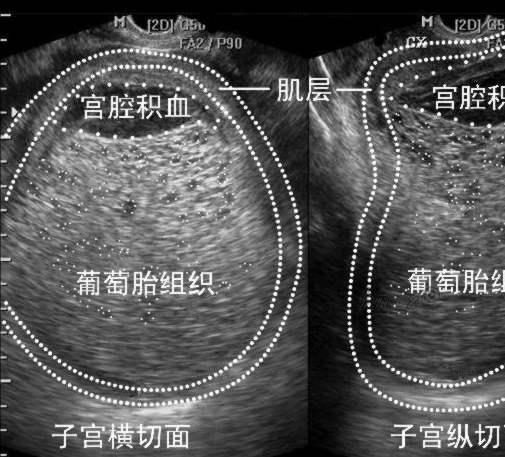

葡萄胎是由于增氧层细胞增生和绒毛间质水肿,使绒毛变成了大小不等的一串水泡,相互之间有细蒂相连接,看起来像葡萄的形状,所以叫做葡萄胎,也叫做水泡状胎块。

葡萄胎的检查主要是靠B超,没有胎心和羊水,出现密集的中低小波,另外就是尿和血hcg测定。经过确诊就应该住院治疗,我们当初前妻就是葡萄胎,不过没有住院,时间过得有点久,我记不得了,好像是吃药打胎,在医院进行的,直接拿掉了。